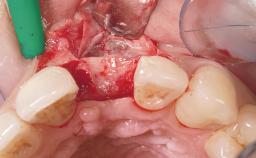

| Placement Protocol | Immediate implant placement |

| Socket Integrity | Damage to one or more bone walls |

| Bone Volume | Damage to one or more socket walls |

| Risk of Complications | High |